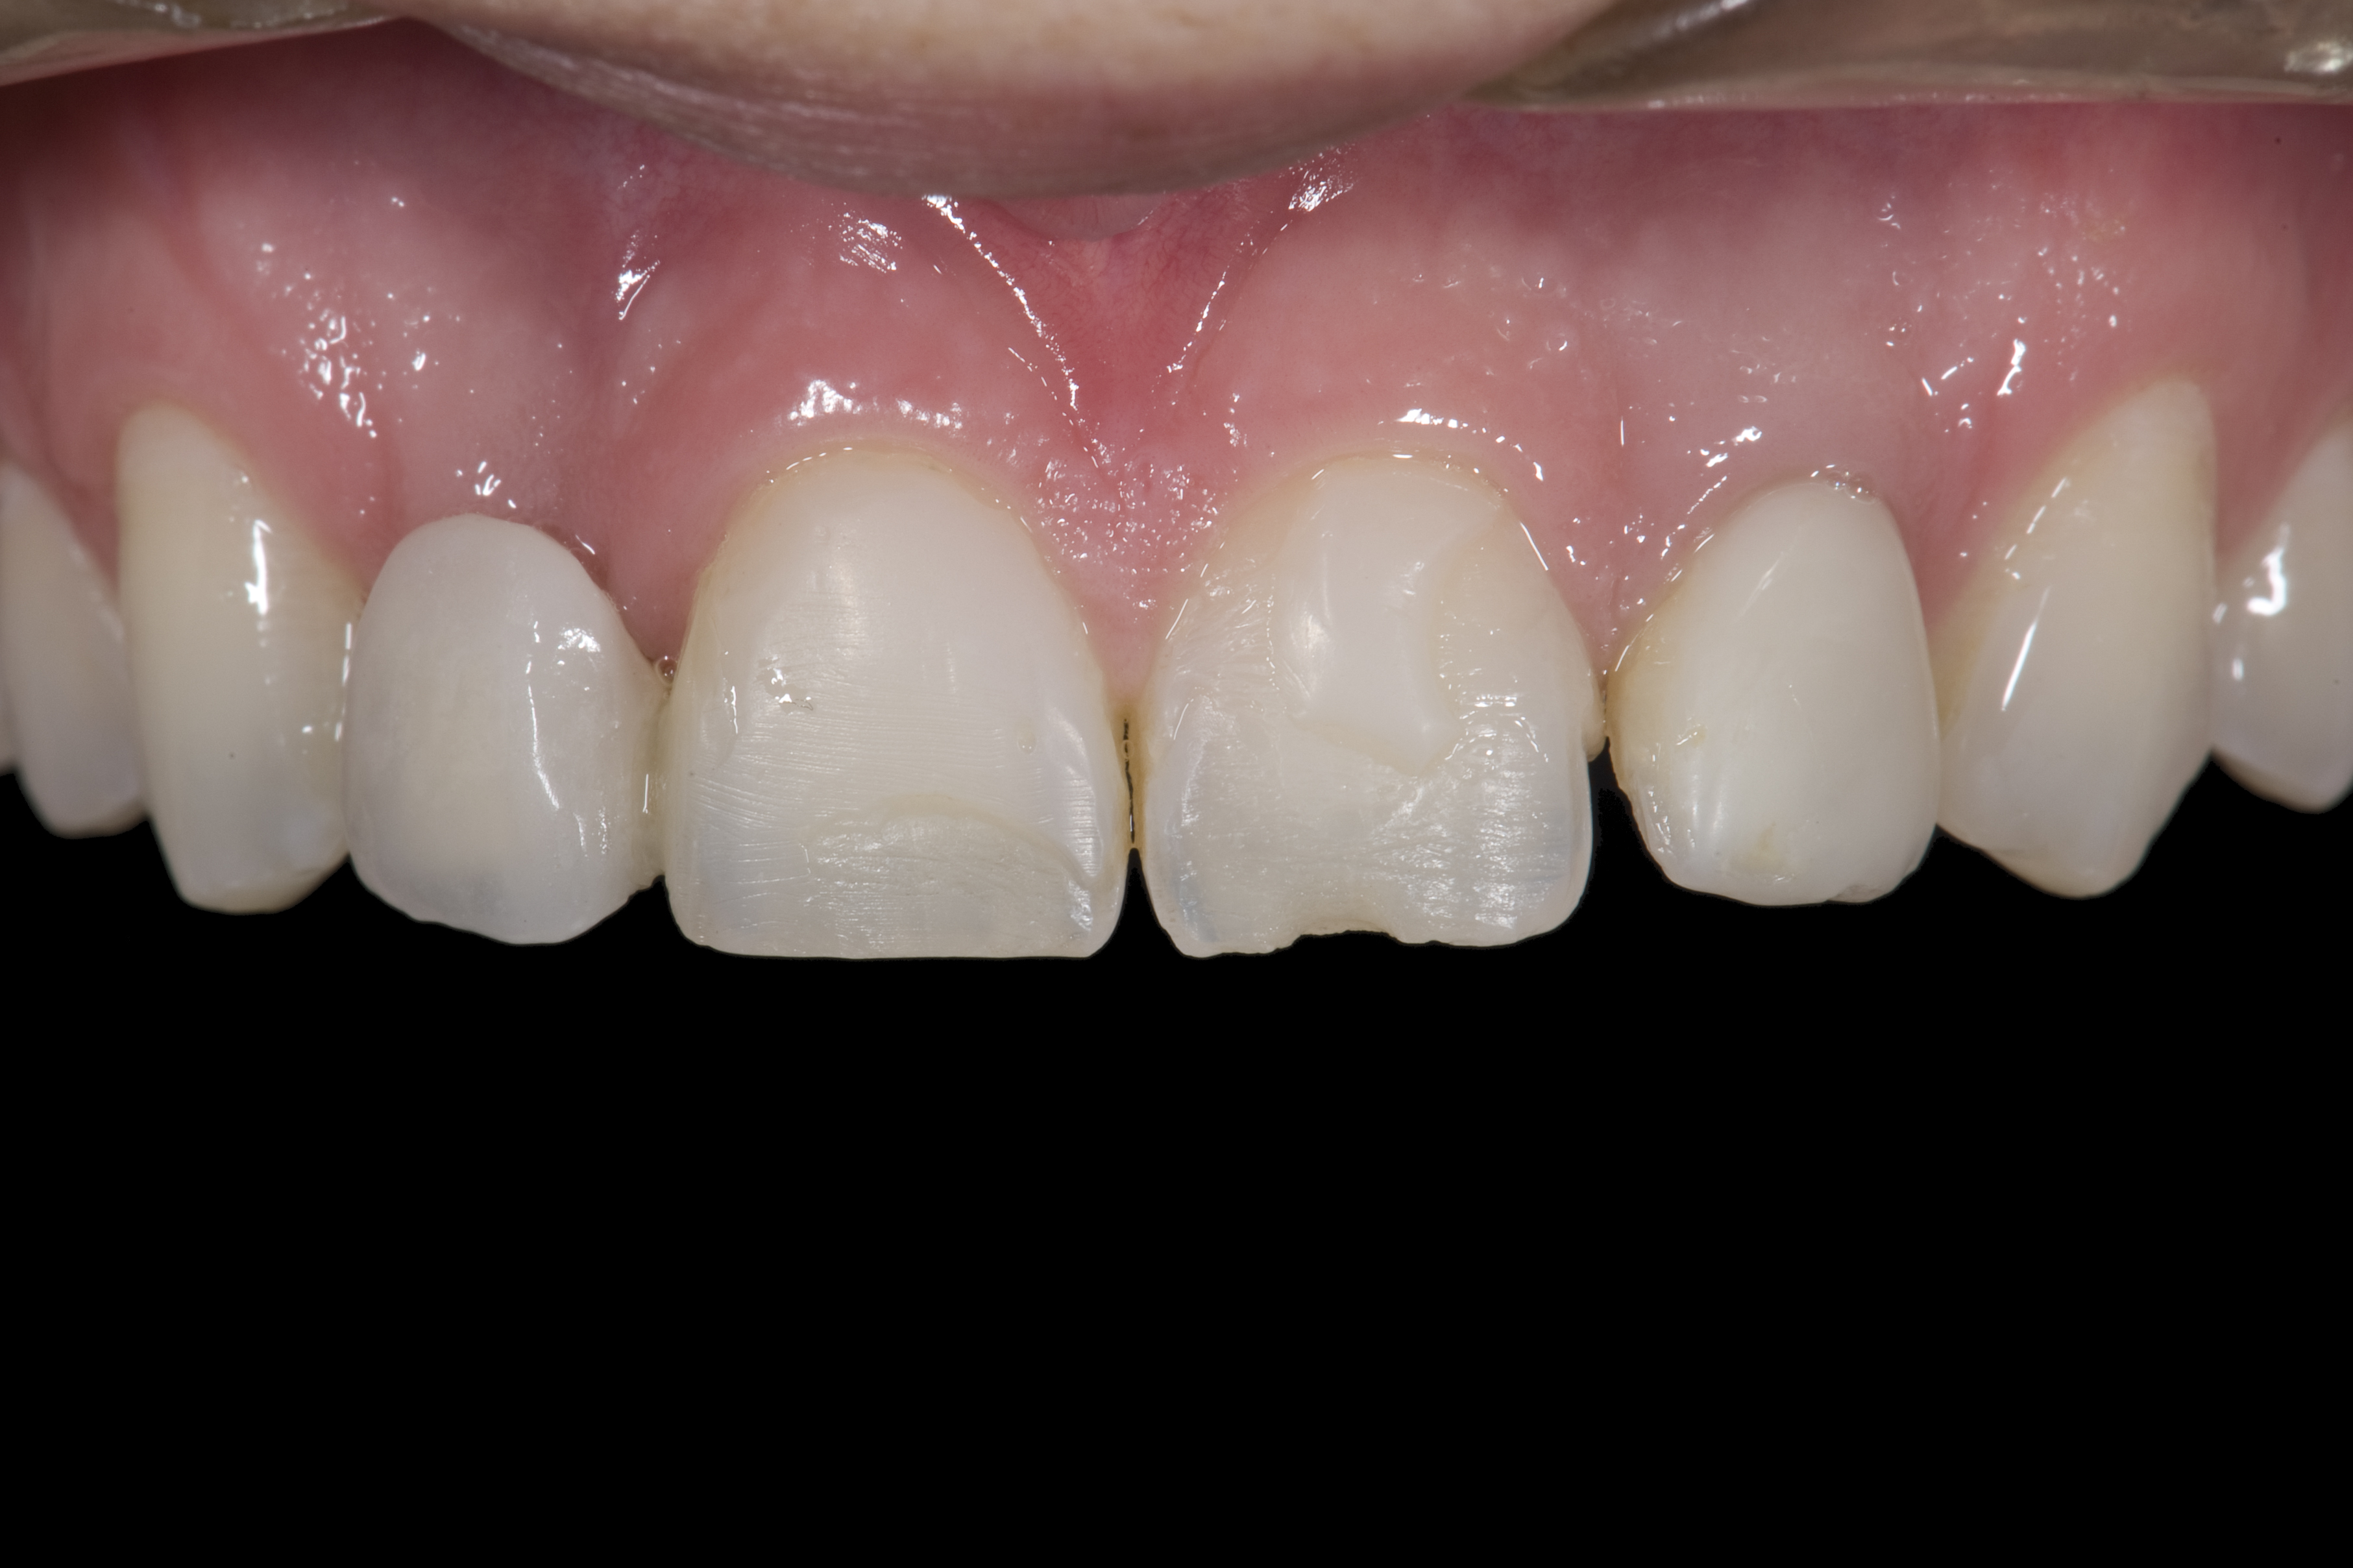

(4.) Double-wing metal resin-bonded (Maryland) bridge replacing the right lateral incisor (facial view).

Figure 4

A 14-year-old patient presented to the office with his mother (Figure 1). His chief complaint involved the large spaces between the teeth created by his missing right maxillary lateral incisor and his small left maxillary lateral incisor. He desired to replace the missing tooth with an implant and create a beautiful smile. Upon examination, he was found to have a class I canine and molar relationship, but because he had a tooth size/arch size discrepancy and space distal to the right central incisor, the remaining incisors had drifted to the right. The left maxillary lateral incisor was peg-shaped and in a cross bite position. Studies have shown a clear association between congenitally missing teeth and reduced tooth size.59-62 Because he was only 14 years old at the time and could not have implants placed until the cessation of growth (somewhere in the vicinity of 22 years old), he was sent to the orthodontist for alignment of the teeth.16,17 After 2 years of orthodontics, the appliances were removed, and his tooth coloration was improved using carbamide peroxide bleaching (Figure 2). Because some form of provisional needed to be placed until he was finished growing, a double-wing metal resin-bonded bridge was chosen. As discussed earlier, this is the ideal transitional prosthesis for patients that have congenitally missing maxillary lateral incisors. The benefits of this type of prosthesis include its ability to be removed and rebonded during the surgical phase of treatment and its ability to retain the roots in their proper position after orthodontic treatment.16 The final plan for the patient was to increase the width of the central and the maxillary left lateral incisor, utilizing porcelain laminate veneers to achieve the appropriate width/length ratio of 80%. A wax-up was created to idealize tooth size, a putty matrix was made from the wax-up to facilitate bonding of the incisors, and a non-precious, double-wing metal resin-bonded bridge was fabricated for lateral incisor replacement. Once the teeth were bonded to ideal size, the “Maryland Bridge” was fabricated from a polyvinyl arch impression with the newly bonded teeth (Figure 3). The metal frame was cast from a non-precious alloy to allow for fabrication of a very thin frame and to create a better surface for bonding. After sandblasting the internal aspect of the frame with CoJet™ silica (3M ESPE), accomplishing salinization, and executing cementation with a dual-cure resin cement, a fairly good adhesion to the frame was anticipated.29 The enamel surface was etched with phosphoric acid for 30 seconds, the primer (Single Bond Plus, 3M ESPE) was applied to both the internal surface of the sandblasted framework and the etched enamel, and the bridge was cemented with RelyX™ ARC (3M Espe) dual-cured resin cement (Figure 4 and Figure 5).